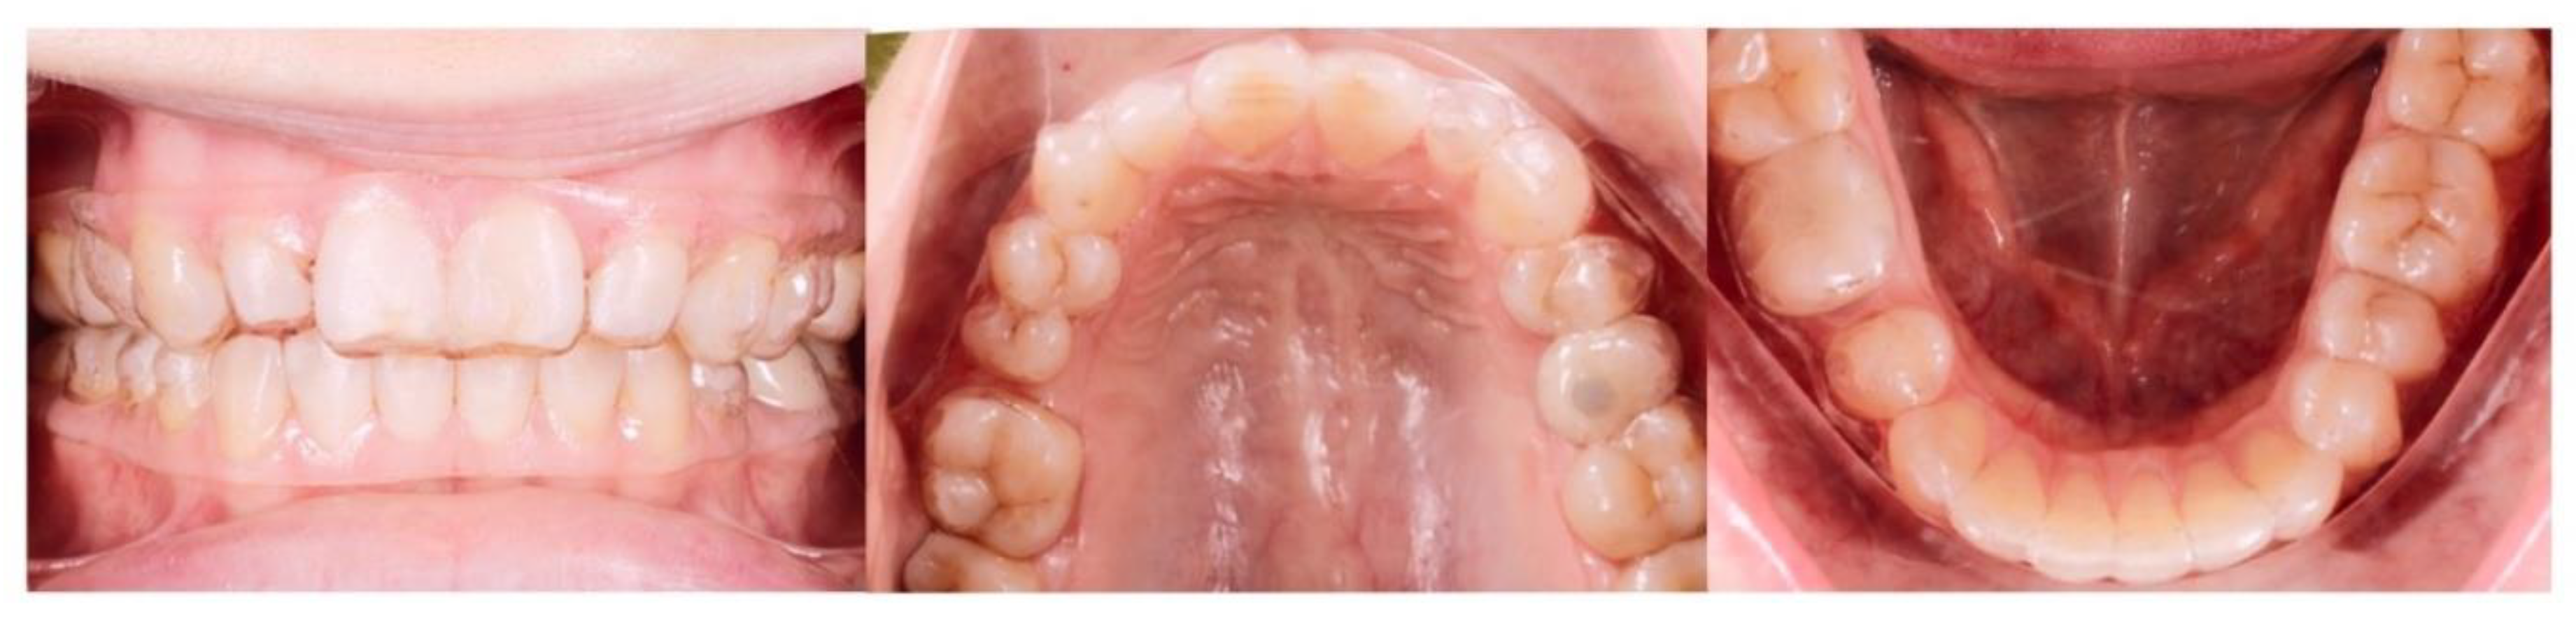

Pre-treatment extra- and intraoral photographs along with the CBCT were analyzed to determine the presence of any pre-existing skeletal, functional, dento-alveolar, and dental asymmetries.

Facial analysis: pre-existing facial asymmetry with the lower third of the face midline (chin alignment) shifted to the left side was noted. Reduced lower third of the face height and retruded profile were distinct features of the pre-treatment facial analysis. (Figure 1 and Figure 2).

Figure 1. Pre-treatment extra- and intraoral photographs showing facial asymmetry with chin shifted to the left side, mandibular midline shifted 2.5 mm to the left compared to the maxillary dental midline which coincides with the facial midline. Occlusal intraoral photographs show multiple microdentic teeth including peg-shaped ##7, 10, microdentic #13, #20, missing #21, implant crown #4: A- extra-oral view in repose, B- extra-oral view smiling, C - extra-oral profile, D - intra-oral views.